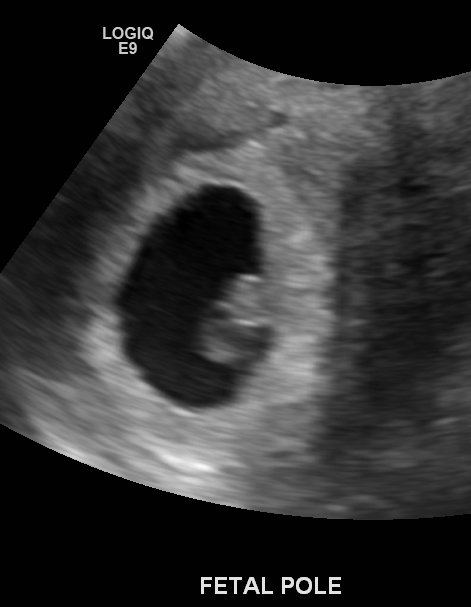

I picked up the CD from my ultrasound and also got a report.

The gestational sac is 1.7x2.02x1.83cm which corresponds to  gestational age of 6 weeks 2 days.

The fetal pole has a crown to rump length of 0.59cm which corresponds to a gestational age of 6 weeks 3 days.

Cardiac activity with a regular rate of 129 beats per minute detected. A well-formed yolk sac is present.

There is a small hypoechoic regional along the left and superior margin of the gestational sac measuring 1.14 x 0.30 x 0.84cm which may be a subchorionic hemorrhage.

Uterus is 9.8x4.3x4.5cm. Cervix is closed and measures 3.8cm.

Right ovary measures 4.7 x 3.0 x 3.1 and the left 3.3 x 2.6 x 2.1cm. Both ovaries contain follicles. Mass in right ovary is 3.2 x 2.1 x 2.0...this may reflect an ovarian cyst. Complex thick walled hypoechoic mass in the left ovary measuring 1.9 x 1.7 x 1.7cm. This is likely a corpus luteal cyst.

Due date estimated: July 10, 2013

And now, for the pics!